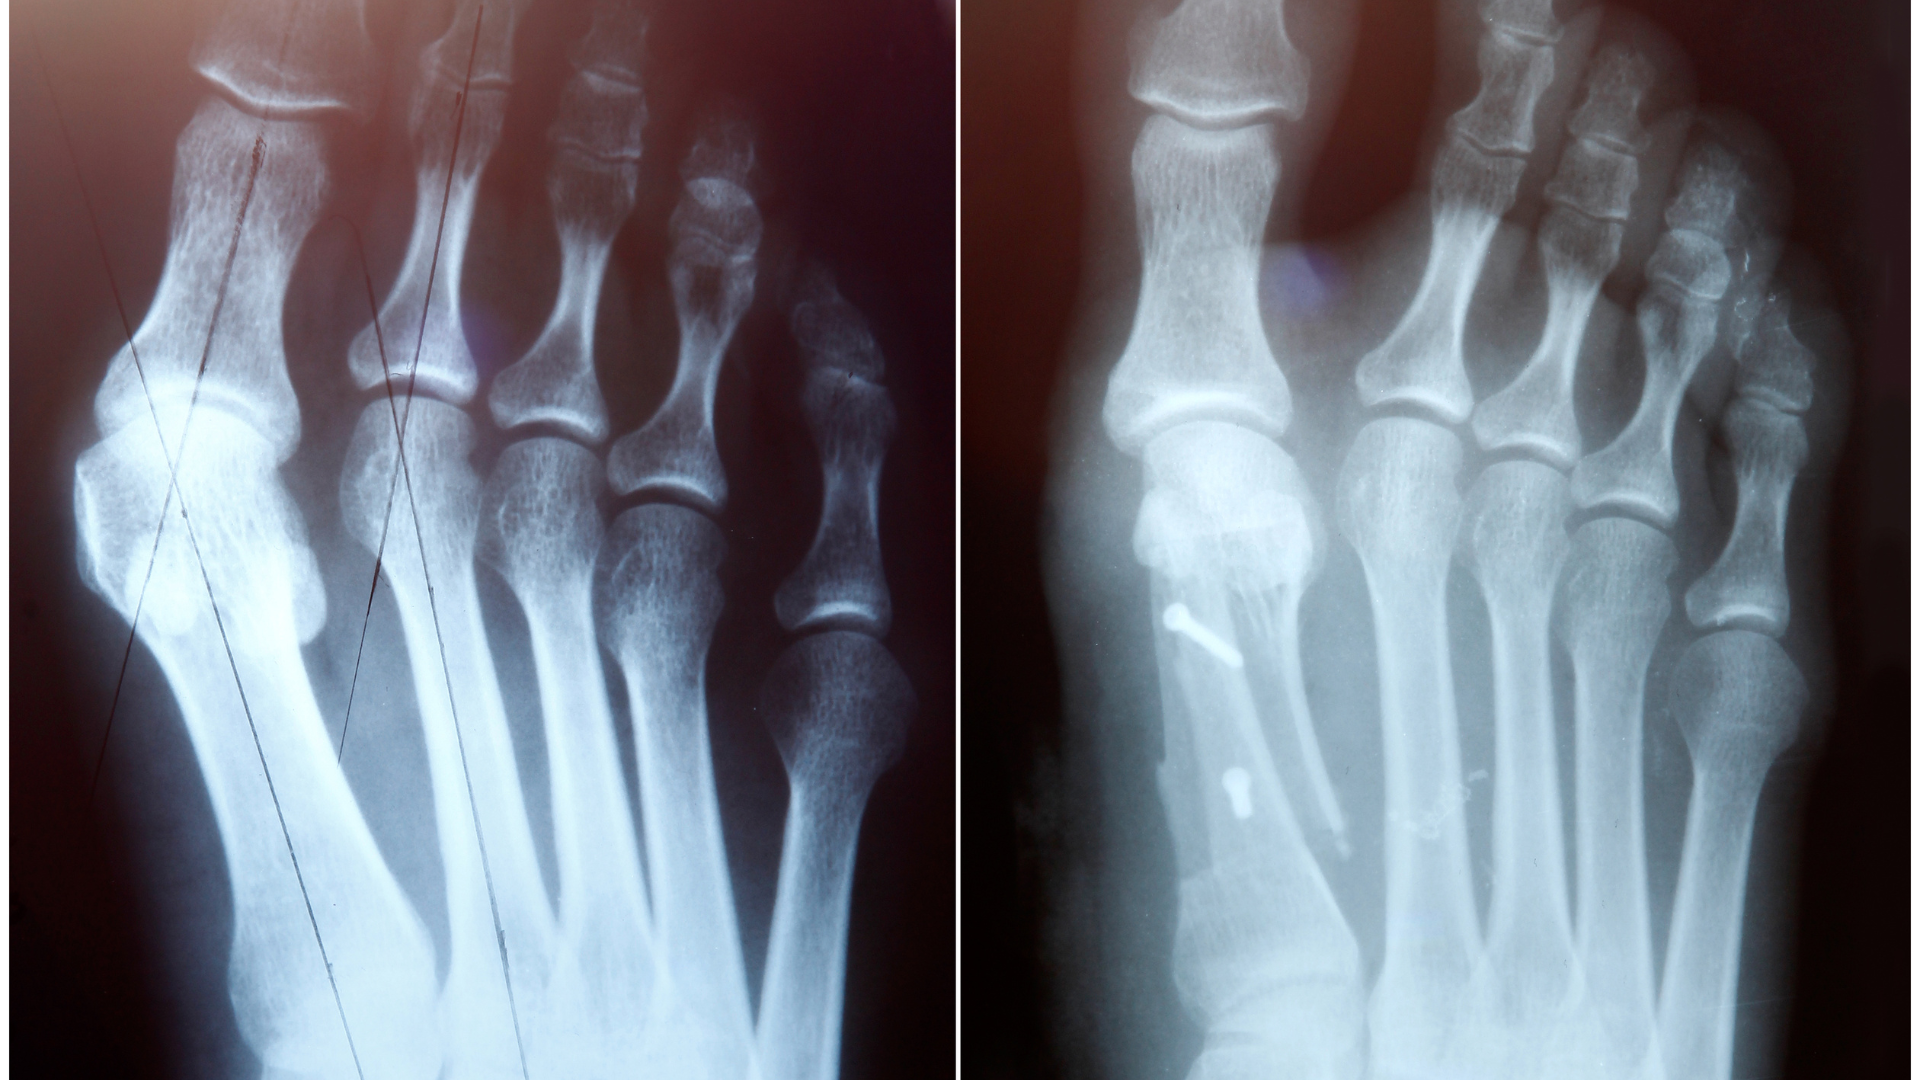

- Chụp X-quang, chụp CT, MRI: Giúp phát hiện các tổn thương điển hình do vi khuẩn lao gây ra trên xương, ví dụ mật độ xương giảm, sụn khớp nham nhở, co rút cơ, hình ảnh ổ khuyết ở đốt sống.